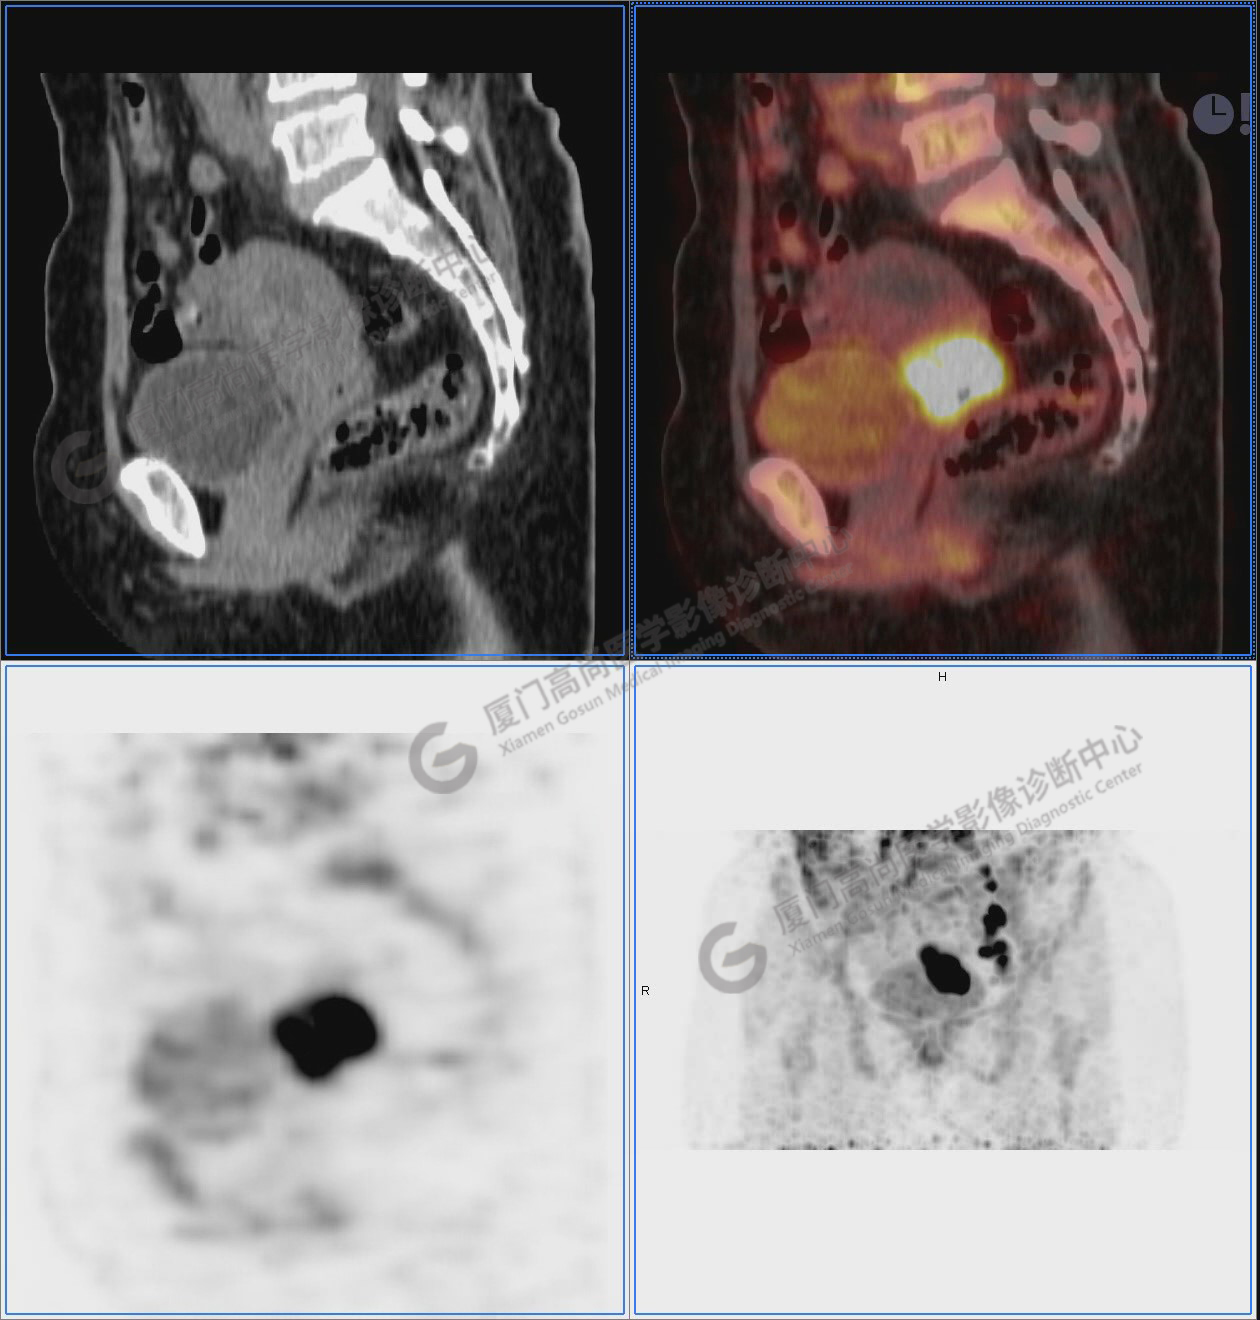

圖10-11:子宮頸軟組織腫塊,代謝異常增高,考慮為宮頸癌。

圖10

圖11

圖12-13:延遲2小時后,宮頸腫塊糖代謝進一步增高。

圖12

圖13